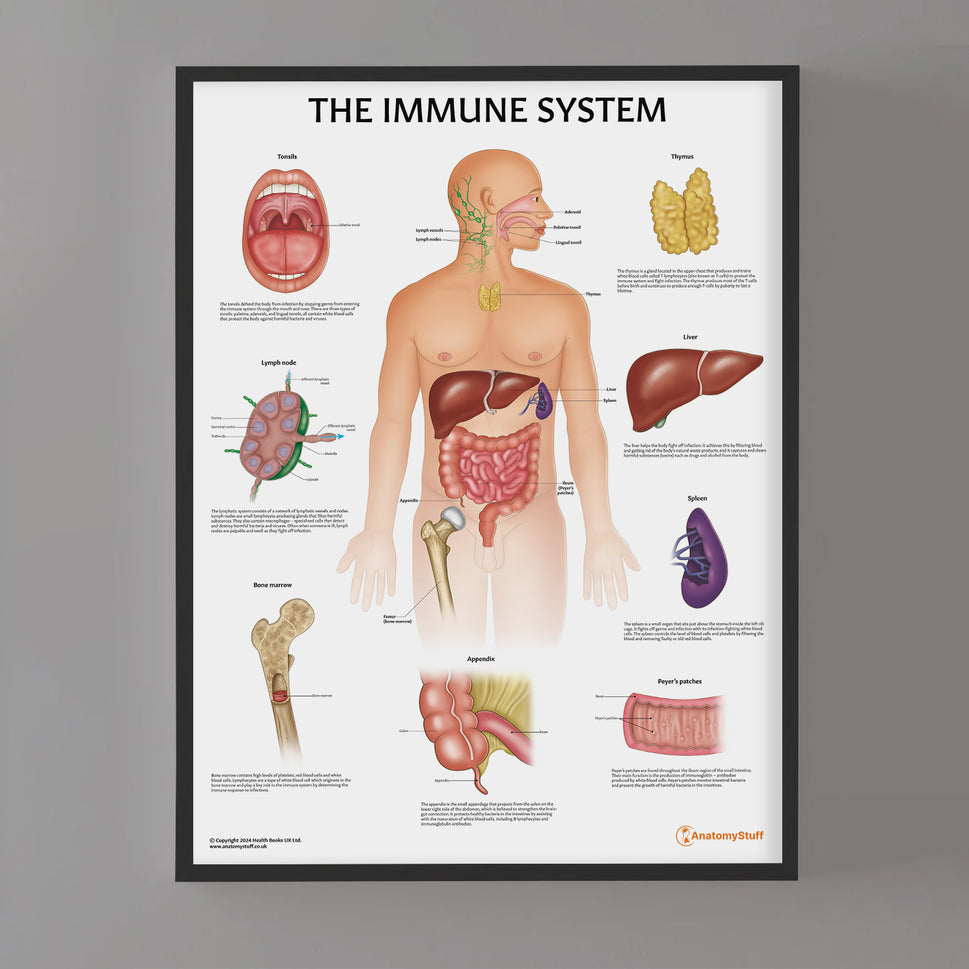

Enhance medical education with our collection of digestive system anatomical models including the stomach, liver, gallbladder, pancreas & colon models. Discover the anatomy of healthy organs as well as common gastrointestinal diseases such as stomach ulcers, gallstones and liver cirrhosis. Our digestive system anatomy posters are ideal for study and patient education.

At AnatomyStuff we stock a diverse range of digestive system anatomical models to suit your training needs. From budget models and affordable medical education posters to highly advanced 3D printed bowel models, you can transform medical training and patient education. As well as our own exclusive collection, we are proud resellers of 3B Scientific, Anatomy Lab, Denoyer-Geppert Science Company, ESP Models, Erler Zimmer and GPI Anatomicals. Explore our exclusive collection of digestive system anatomy charts, posters, fine art prints and digital anatomy study guides. Discover the anatomy of key organs like the liver, stomach, pancreas and bowel as well as the pathophysiology of common conditions like peptic ulcer disease, coeliac disease, IBD and much more. We have anatomy posters suitable for school children all the way up to medical degree level. From a liver anatomy poster to a digital study guide all about common GI disorders, find exactly what you need right here to enhance medical training and patient education.